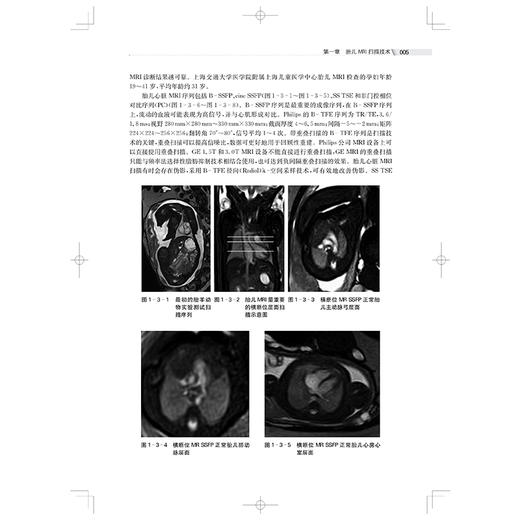

本书从胎儿各系统疾病(神经系统、颜面部及颈部、呼吸系统、泌尿生殖系统、消化系统、前腹壁畸形及其他腹部异常、四肢系统、心胸循环系统等)的概述入手,结合典型病例,叙述胎儿的发育及其正常和异常MRI表现,以大量的典型图像、详细的标注和说明展示各个孕周胎儿疾病的MRI,图文并茂,再进一步分析,举一反三,让学习者从中获得最大的收获,对从事胎儿磁共振的影像科医师和新生儿医师、产科医师都有帮助。